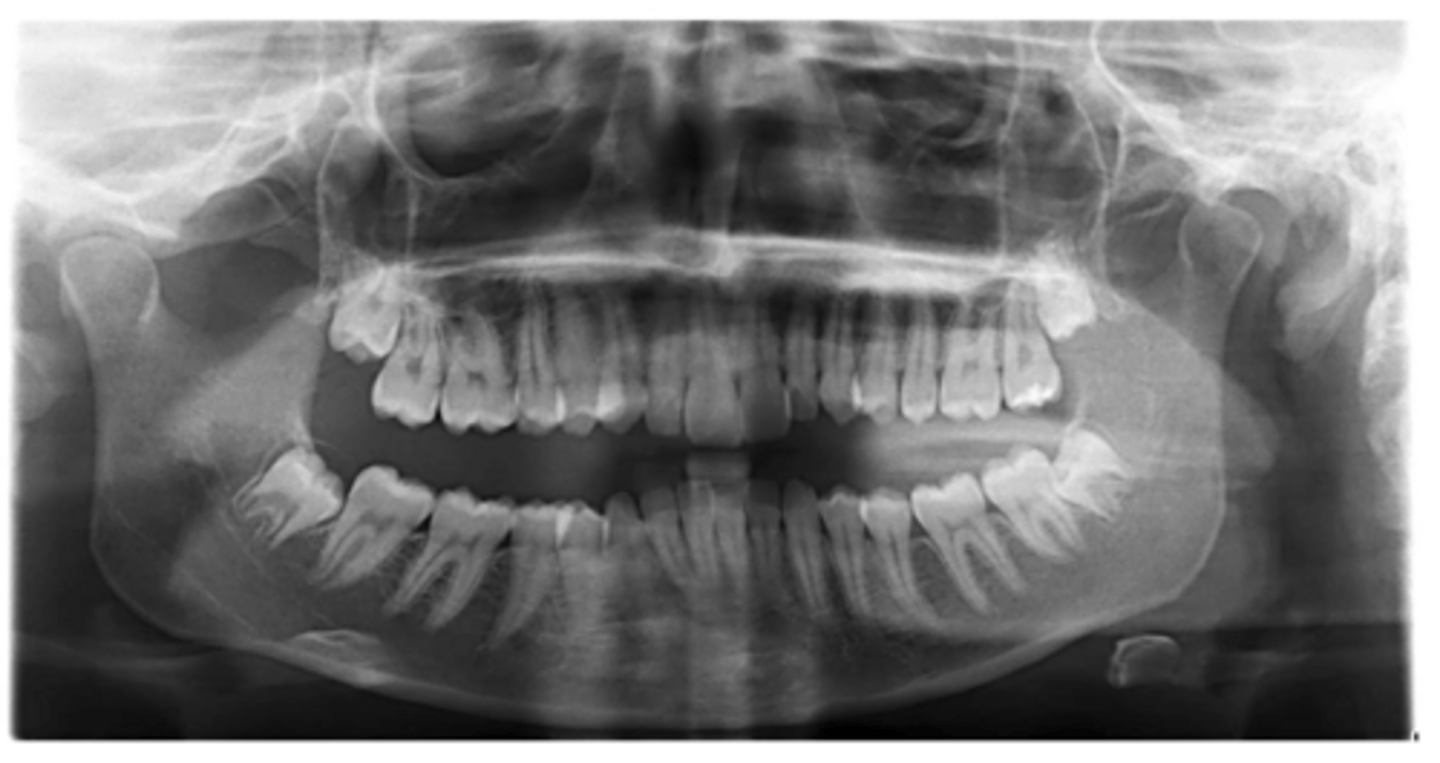

Class II skeletal (very light)

What type of skeletal malocclusion is this patient?

Hypodivergent

Are the hyper-, hypo-, o normo- divergent?

proclined

Maxillary incisors are?

Class II

Hyperdivergent

Class I

Normodivergent

No

Are the maxillary incisors proclined/flared?